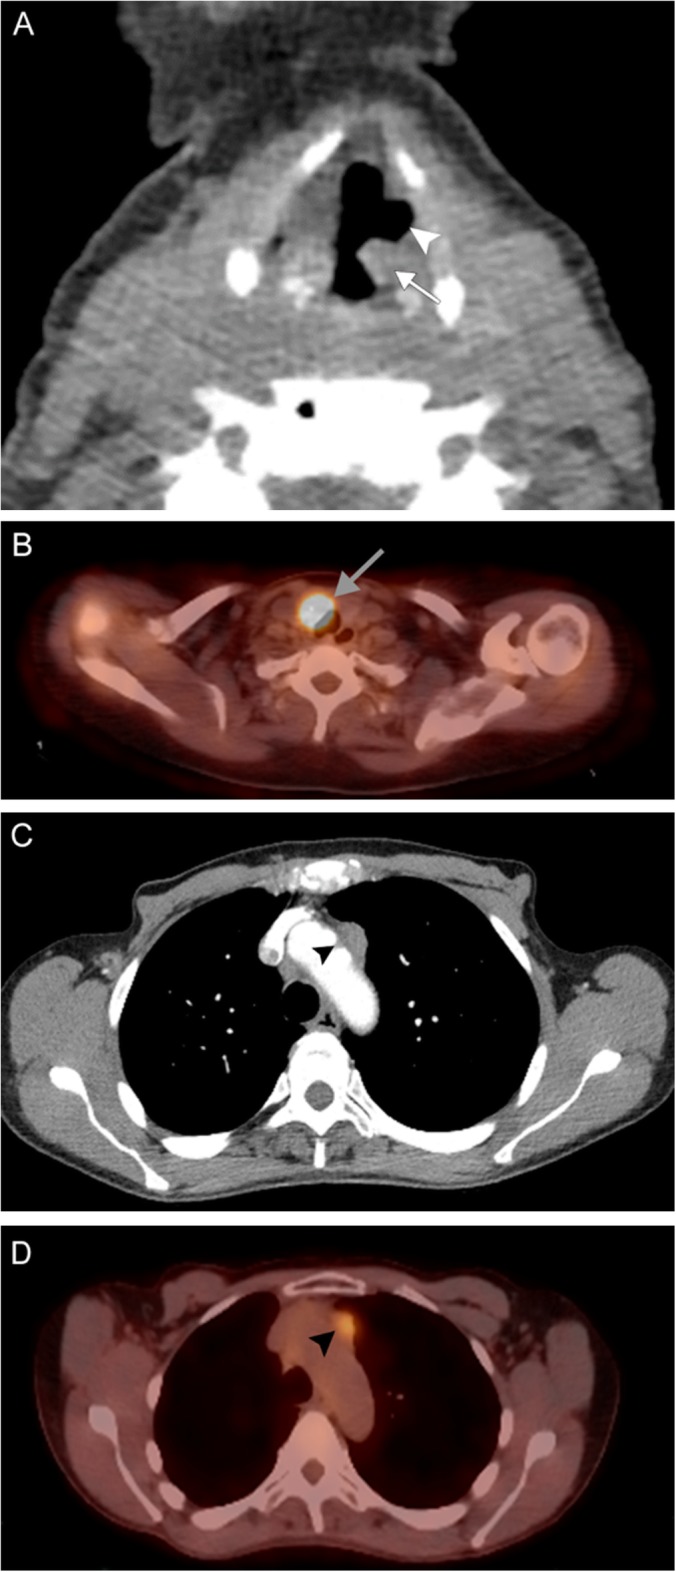

Fig. 19.

Lung cancer. A 79-year-old woman with 55-pack-year smoking history presenting with hoarse voice and chronic vomiting. Coronal contrast-enhanced images of the larynx (a) and lungs/mediastinum (b) reveal medialization of the left vocal fold (white arrow) with dilation of the ipsilateral piriform sinus (white arrowhead). A large mass centered in the left upper lobe extends into the aortopulmonary window and also encases a vessel (black arrow). These findings are consistent with left vocal cord paralysis due to compression of the left recurrent laryngeal nerve in the setting of stage IV lung cancer

Fig. 20.

Metastatic mediastinal lymphadenopathy. A 59-year-old woman with right breast cancer status post chemoradiation completed 5 years prior presents with rapidly progressive hoarseness. An axial non-contrast CT image (a) demonstrates anteromedial rotation of the left posterior vocal fold and arytenoid cartilage (white arrow) with associated left-sided dilatation of the laryngeal ventricle (white arrowhead). Associated PET image (b) demonstrates compensatory FDG uptake in the contralateral vocal fold (gray arrow). Contrast-enhanced CT (c) and PET (d) images more inferiorly reveal hypermetabolic prevascular lymphadenopathy in the superior mediastinum (black arrowheads). Overall, these findings are consistent with left vocal cord paralysis due to compression of the left recurrent laryngeal nerve by a metastatic prevascular lymph node